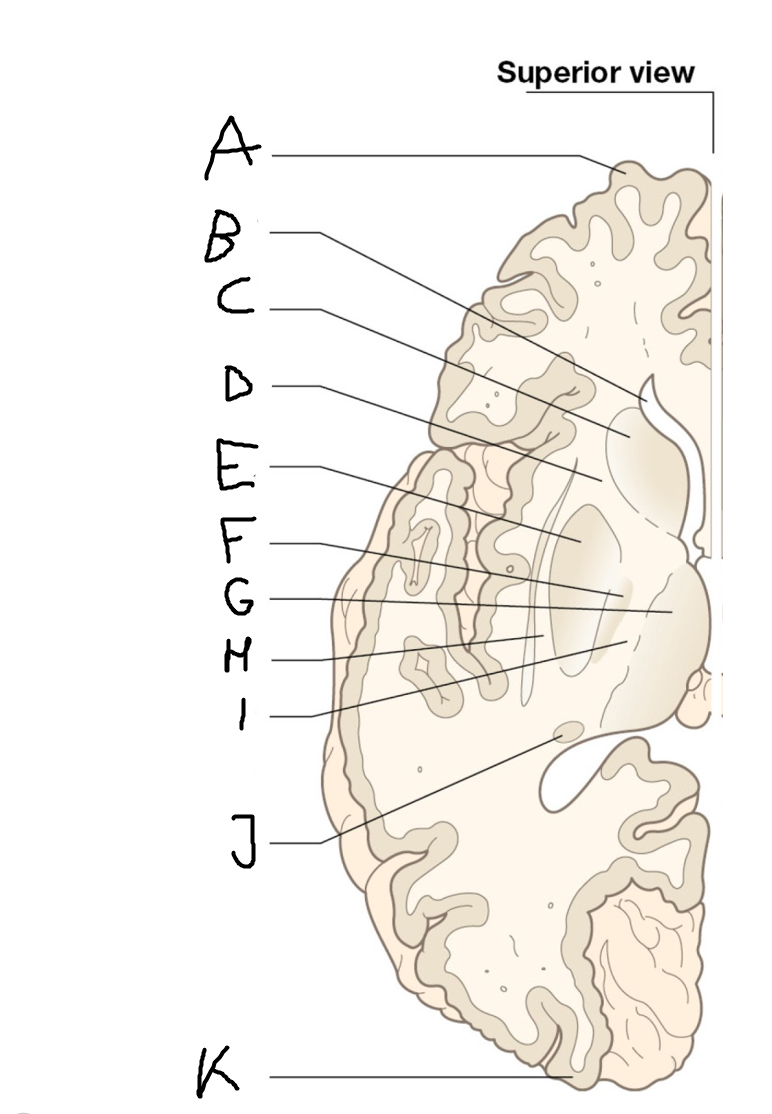

internal capsule (posterior limb)

B

anterior horn of lateral ventricle

C

head of caudate nucleus

D

internal capsule (anterior limb)

E

putamen

F

globus pallidus

G

Thalamus

H

External capsule

I

internal capsule (posterior limb)

J

tail of caudate nucleus